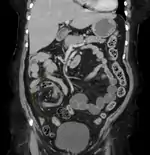

CT scan of a cecal volvulus

CT scan of a small bowel volvulus. It shows two juxtaposed segments of narrowing, which is the spot of mesentery rotation. The other signs indicate strangulation.